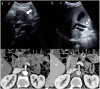

The incidence and mortality of pancreatic ductal adenocarcinoma are growing over time. The management of patients with pancreatic ductal adenocarcinoma involves a multidisciplinary team, ideally involving experts from surgery, diagnostic imaging, interventional endoscopy, medical oncology, radiation oncology, pathology, geriatric medicine, and palliative care. An adequate staging of pancreatic ductal adenocarcinoma and re-assessment of the tumor after neoadjuvant therapy allows the multidisciplinary team to choose the most appropriate treatment for the patient. This review article discusses advancement in the molecular basis of pancreatic ductal adenocarcinoma, diagnostic tools available for staging and tumor response assessment, and management of resectable or borderline resectable pancreatic cancer.